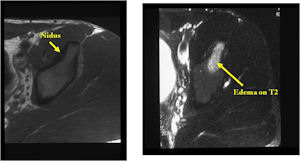

MRI:

- MRI should be performed with gadolinium if possible. The nidus should enhance with gadolinium

- An osteoid osteoma on MRI may mimic findings of a malignant tumor such as Ewing’s sarcoma or osteomyelitis because of the presence of marrow and soft tissue edema that can be extensive and make it difficult to discern a nidus.

- CT is more useful for detecting the nidus if there is extensive edema

- Osteoid Osteomas are Intermediate intensity on T1

- High intensity on T2 in areas of nidus and surrounding edema

- Reactive marrow edema may obscure the lesion on T2

- MRI is good for detecting synovitis and joint effusion with intraarticular osteoid osteomas